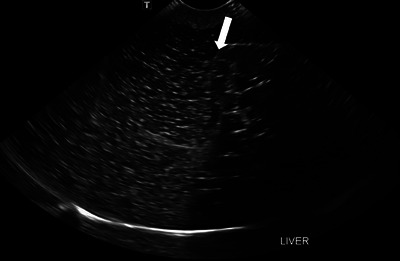

Ultrasonography in veterinary medicine serves a vital role in the diagnosis and management of various medical conditions by allowing noninvasive visualization of internal structures. Veterinary students face many challenges in gaining hands-on experience with ultrasound equipment and developing competencies in ultrasonography. This is largely due to the limited access and ethical dilemmas of live animal models and the high cost of commercial phantoms. To solve these issues, the niche of cost-effective amateur models has exponentially increased. However, while these at-home models solve the financial issues associated with commercial phantoms, they still lack the realism and fidelity necessary to simulate the real-time feedback needed to gain the spatial awareness of this dynamic imaging modality. To foster successful day-one-ready veterinary students, The Ohio State University College of Veterinary Medicine acknowledged that a better solution should be possible. A prospective anatomic study was performed to recognize the imaging anatomy and usability of a new model termed the Danny Phantom. This model was developed by testing various amateur phantom materials from both the literature and self-discovered. These materials were analyzed and deemed satisfactory versus unsatisfactory based on fulfillment of predetermined criteria of an ideal phantom model. It was determined that real fixed organs can be encased in traditional bovine gelatin to produce an ultrasound phantom with recognizable parenchyma. Other additives can be included to give the phantom an imitated peritoneal space and prevent spoilage of the gelatin for an extended period of time.